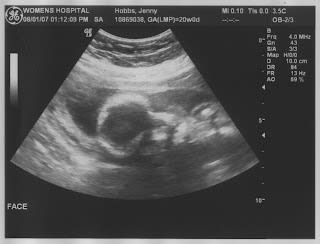

Mouth Opened